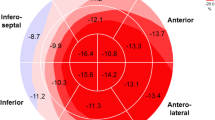

The results of global strain measurement are shown in Table 2 and Fig. 1. There were no significant differences between the groups. In a detailed analysis, there was no correlation of global strains with the pulmonary sarcoidosis stage (all p > 0.10, all r between − 0.15 and 0.15). All global strains correlated with the ejection fraction in the sarcoidosis patients (GLS: r = − 0.42, p < 0.001; GCS: r = − 0.65, p < 0.001; GRS: 0.31, p = 0.001). In all cases, the absolute value of the strains were positively correlated with the EF (GLS and GCS were expressed as negative numbers). However, correlations were similar in the control subjects (GLS: r = − 0.18, p < 0.42; GCS: r = − 0.70, p < 0.001; GRS: 0.38; p = 0.08) and there was no significant difference between correlations in the sarcoidosis patients and controls (GLS: p = 0.29; GCS: p = 0.71; GRS: p = 0.75). The data for strain values in the sarcoidosis patients divided into quartiles according to EF are shown in Table 3.